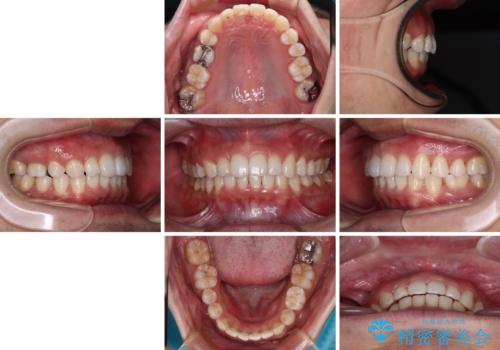

右上と左下は永久歯が欠如しており、大きさの大きく異なる乳歯が残存していたため、奥歯の咬み合わせを構築するために苦労しました。

元々隙間の空いていた上顎の正中は、後戻りのリスクが高いため、下顎前歯同様ワイヤー固定を行いました。